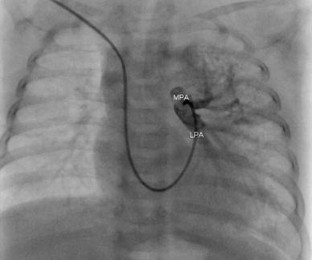

Absence of the Right Pulmonary Artery Associated With a Partial Anomalous Pulmonary Venous Connection

Unilateral absence of a pulmonary artery is a rare anomaly. Patients may present with hemoptysis, recurrent respiratory infections, pulmonary hypertension, or congestive heart failure. This report describes the case of a missing right pulmonary artery associated with anomalous left pulmonary venous connection not previously described in the medical literature.

Fig. 1